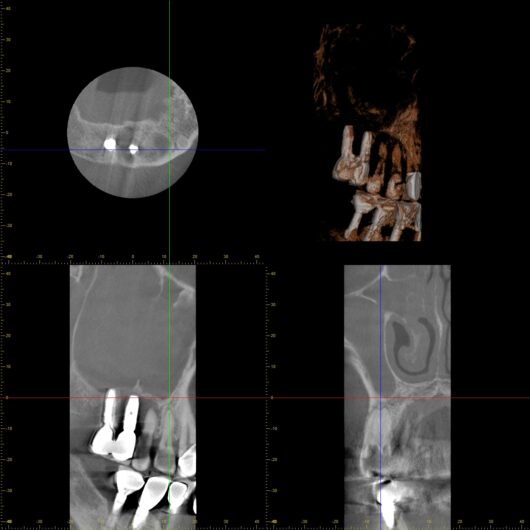

真実を明らかにするため、すぐに精密な歯科用CT撮影を行いました。モニターに映し出された画像は、衝撃的なものでした。

(※本来は黒く映る空洞が、炎症で真っ白になっている様子)

通常、空気で満たされているはずの上顎洞はCTでは「黒く」映ります。しかし、この患者さんの画像では、上顎洞が炎症による膿と粘膜の腫れによって完全に「真っ白」に埋まっていました。

そしてその炎症の起点は、重度歯周病に侵された歯と、細菌感染を起こしたインプラントの根元にありました。これこそが「歯性上顎洞炎」の正体です。

どんなに鼻から薬を入れても、原因である「歯の感染源」を取り除かない限り、この炎症が治まることはありません。MRIは「結果」としての炎症を映し出しましたが、その「原因」が歯にあることまでは指摘できなかったのです。